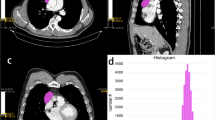

All data were analyzed on a GE ADW4.6 workstation. The mean ADC values were measured independently by one experienced radiologist (B.L., with 15 years of experience in MRI) using a commercial software (Functool 9.4.05, GE Healthcare). He was aware that the patients had TETs, but blinded to the pathological subtypes of the tumors. First, he reviewed the conventional MR images carefully to determine the solid part of each tumor. Next, the DWI data were analyzed. Two circular regions of interest (ROIs) were manually drawn using an electronic cursor in the slice containing the largest cross-sectional area, which were placed to include the solid tumor elements by defining ROIs based on the relatively high signal intensity on the DW image (bright region, b = 1000 s/mm2, as shown in Fig. 2a) or the relatively low ADC value in the ADC map (deep-blue region, as shown in Fig. 2b), avoiding large vessels and hemorrhagic, cystic, and necrotic areas. The mean ROI area was 46.9 ± 20.2 mm2 (range, 11.5–88.0 mm2). The ADC value was calculated by fitting the b0 image and DW images at 1000 s/mm2b value into the conventional ADC equation (Eq. (1)) [28]:

The schematic diagram of tumor segmentation. Two circular regions of interest were drawn to include the solid tumor elements by defining ROIs based on the relatively high signal intensity on the DW image (a, bright region, b = 1000 s/mm2), or the relatively low ADC value in the ADC map (b, deep-blue region), and a volume of interest (VOI) was drawn around the entire cross-sectional tumor region in three consecutive slices on DW images (c)

The ADC maps were generated automatically (as shown in Fig. 2b) and the mean ADC values within two ROIs were obtained. The final ADC is the average of the ADC values of two ROIs.

All images were anonymized and stored in DICOM format. One experienced radiologist (B.L., with 15 years of experience in MRI) manually segmented the tumor area on axial DW images by using commercial software applications, NordicICE (Version 4.0.4, NordicNeuroLab). A volume of interest (VOI) was drawn manually around the entire cross-sectional tumoral region in three consecutive slices containing the largest cross-sectional area on DW images in a slice-by-slice method. Care was taken to exclude adjacent tissues, attempting to maintain an approximate distance of 1–2 mm away from the tumor margin to minimize the partial volume phenomenon (Fig. 2c).